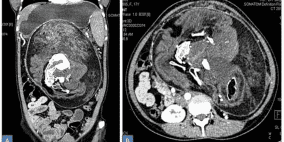

عانت من آلام بالمعدة.. والأطباء اكتشفوا المفاجأة الصاعقة